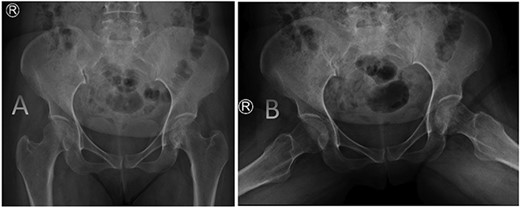

A medically free 42-year female presented to our institute as a life-saving case from a different hospital as she was a victim of unrestrained road traffic accident 2 days prior to presentation. Upon assessment in the emergency department (ER), she was conscious and oriented, and was found to have bilateral lung contusion, and multiple fractures of ribs. She also had a left sided vertical femoral head fracture dislocation comprising around 40% of the femoral head (Fig. 1). Closed reduction under conscious sedation was done in the ER, which was successful based on post-reduction imaging studies (Fig. 2). Her chest injuries were treated with chest tube and observation for 10 days. During that time, discussion was made with the patient regarding her situation and conservative management was chosen by way of bed rest and continuation of skeletal traction for 4 weeks with serial radiographs in the hospital on a weekly basis after clearance of her chest injuries. Skeletal traction was discontinued and she was advised to continue bed to wheelchair mobilization for an additional 2 weeks. After 6-weeks from the injury, a Computed Tomography (CT) was done to the patient and revealed signs of fracture healing (Fig. 3). At 3-years after the injury, she was found to have full painless range of motion of the affected hip and has resumed her activity of daily living without any complaints and the images showed a symmetrical joint space of the hips (Fig. 4).

AP radiographs (A) and frog leg lateral (B) radiographs at 3-year follow-up showing a concentrically reduced hip.